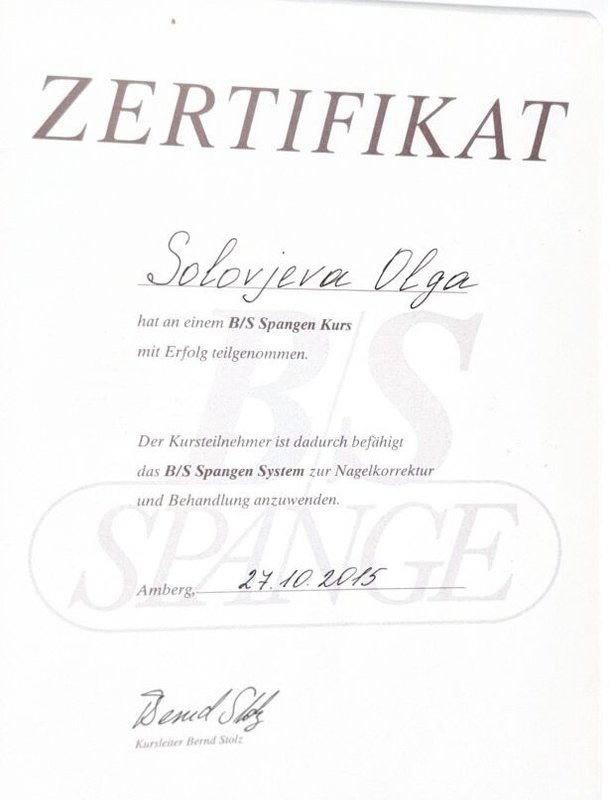

Знаю Ольгу Игоревну давно и уверена в ее профессионализме. Она постоянно учится и помогала мне с проблемами рук и ног, всегда справлялась сама, никого не перенаправляла. Она талантливый и умный доктор, профессионал.